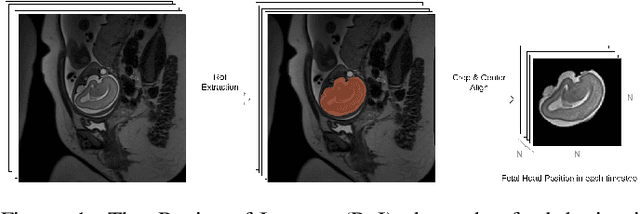

Abstract:Fetal magnetic resonance imaging (MRI) is challenged by uncontrollable, large, and irregular fetal movements. Fetal MRI is performed in a fully interactive manner in which a technologist monitors motion to prescribe slices in right angles with respect to the anatomy of interest. Current practice involves repeated acquisitions to ensure diagnostic-quality images are acquired; and the scans are retrospectively registered slice-by-slice to reconstruct 3D images. Nonetheless, manual monitoring of 3D fetal motion based on displayed 2D slices and navigation at the level of stacks-of-slices (instead of slices) is sub-optimal and inefficient. The current process is highly operator-dependent, requires extensive training, and significantly increases the length of fetal MRI scans which makes them difficult for pregnant women, and costly. With that motivation, we presented a new real-time image-based motion tracking technique in MRI using deep learning that can significantly improve state of the art. Through a combination of spatial and temporal encoder-decoder networks, our system learns to predict 3D pose of the fetal head based on dynamics of motion inferred directly from sequences of acquired slices. Compared to recent works that estimate static 3D pose of the subject from slices, our method learns to predict dynamics of 3D motion. We compared our trained network on held-out test sets (including data with different characteristics, e.g. different age ranges, and motion trajectories recorded from volunteer subjects) with networks designed for estimation as well as methods adopted to make predictions. The results of all estimation and prediction tasks show that we achieved reliable motion tracking in fetal MRI. This technique can be augmented with deep learning based fast anatomy detection, segmentation, and image registration techniques to build real-time motion tracking and navigation systems.

Abstract:Brain segmentation is a fundamental first step in neuroimage analysis. In the case of fetal MRI, it is particularly challenging and important due to the arbitrary orientation of the fetus, organs that surround the fetal head, and intermittent fetal motion. Several promising methods have been proposed but are limited in their performance in challenging cases and in real-time segmentation. We aimed to develop a fully automatic segmentation method that independently segments sections of the fetal brain in 2D fetal MRI slices in real-time. To this end, we developed and evaluated a deep fully convolutional neural network based on 2D U-net and autocontext, and compared it to two alternative fast methods based on 1) a voxelwise fully convolutional network and 2) a method based on SIFT features, random forest and conditional random field. We trained the networks with manual brain masks on 250 stacks of training images, and tested on 17 stacks of normal fetal brain images as well as 18 stacks of extremely challenging cases based on extreme motion, noise, and severely abnormal brain shape. Experimental results show that our U-net approach outperformed the other methods and achieved average Dice metrics of 96.52% and 78.83% in the normal and challenging test sets, respectively. With an unprecedented performance and a test run time of about 1 second, our network can be used to segment the fetal brain in real-time while fetal MRI slices are being acquired. This can enable real-time motion tracking, motion detection, and 3D reconstruction of fetal brain MRI.